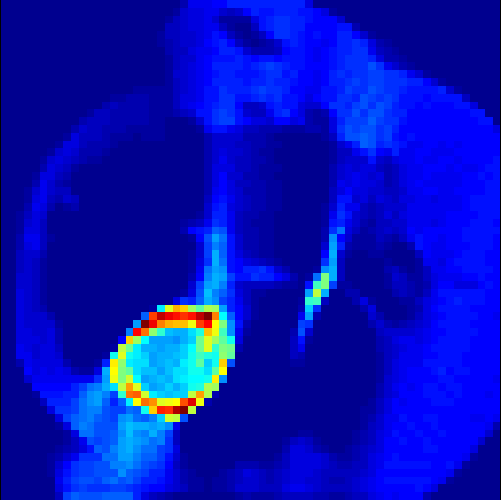

5.2 Monte Carlo Simulation

In order to test the behaviour of the proposed method in a more realistic, random-based test case, we performed a Monte Carlo simulation for dynamic SPECT imaging. First, we created a simple image phantom consisting of an outer and two inner circles which represents the structure of the region of interest (see figure 8(a)). Within those regions we assumed concentration curves over a time period of 90 time steps as displayed in figure 8(b). Based on the tracer intensity in an image frame at each time step, we created a variable number of random decay events (where the number is proportional to the average concentration in one pixel in the whole image frame per time step) with a probability proportional to the concentration in every subregion. They are detected by a virtual double head gamma camera rotating around the patient by 46 degrees per time step, which consists of 374 detector bins. Every simulated decay event is projected onto the scanner and counted by the corresponding detector bin.

In two different tests we fixed the number of events counted by the detector equal to (resp. ) times the average concentration in one pixel. The resulting sinogram images of the accumulated counts in each bin are shown in figure 9.

Based on the sinogram data we applied the proposed algorithm in order to reconstruct the original image sequence. The results for both test cases are shown in figure 10.

As one can see, the method is able to reconstruct the regions properly, even in case of a low count number. Within a number of iterations (average of 100 outer and 10000 inner iterations), the algorithm presents a reasonable reconstruction of the region of interest and the corresponding regional tracer concentration curves. Here, the parameters were not optimized as in the case of the synthesized data sets in the previous section, but kept fixed as , and . With futher optimized parameter values one could possibly provide even better results.